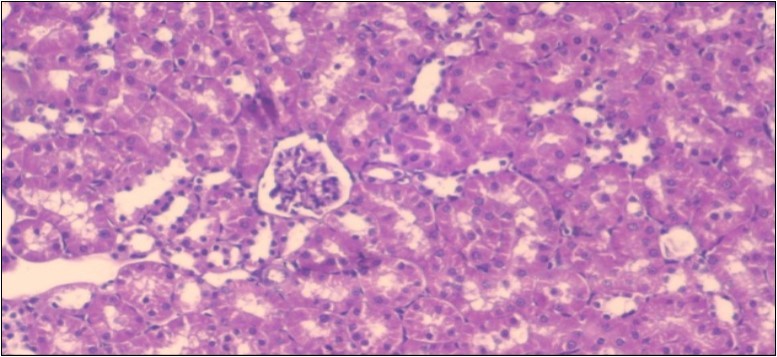

The histological examination of the kidney of the control rats fed on a standard diet showing normal rounded capsules with normal Bowman's glomeruli, round proximal tubules and elongated distal tubules with high cuboidal cells figure 1. The rats fed (HFD) showed fatty degeneration of the tubules with eosinophilic material deposition, glomerular atrophy with wide urinary space and distal tubules with extrusion of nuclei into lumen figure 2. By comparison kidneys of rats which were treated by fennel after being obese and the control rats observed partial improvement in both Bowman's capsules and proximal tubules. Note the distal tubules show less focal fatty infiltration figure 3.While examination of rats kidney that were treated by ator after obesity showed improvement in Bowman's capsules with normal glomerular and partial improvement in proximal tubules and distal tubules, figure 4. Kidney of rats that were treated by fennel and ator after obesity and the control rats showed high improvement in the tissues with normal glomerular and that Most of Bowman's capsules and renal tubules, restoring their normal appearance figure 5.

Figure 3.Photomicrogragh of kidney section of treated rat with fennel herb showing partial improvement in both Bowman's capsules and proximal tubules. Note the distal tubules show less focal fatty infiltration, (H&E) (40X)